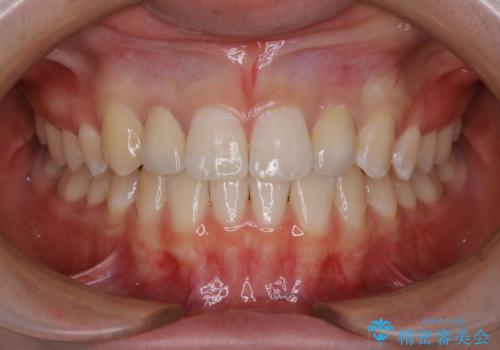

- 元々は矯正治療を主訴にご来院されました。

治療を始めるにあたり、精密検査を受けていただき全体の状況を把握したうえで矯正治療の計画を立てることとなりました。